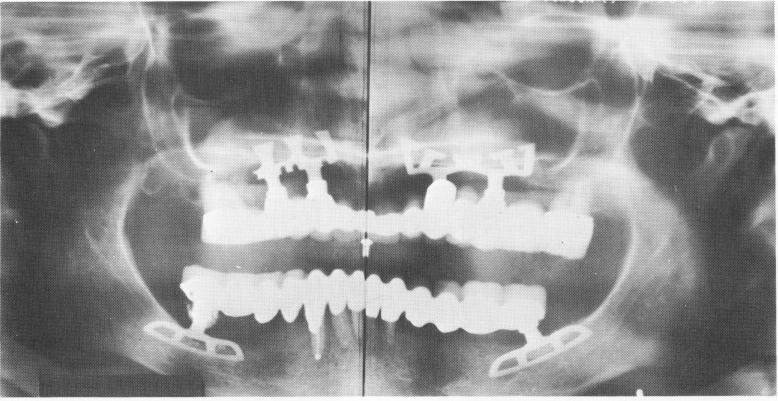

Fig. 11-135. A Panorex of the completed case. Although there are only two blades, each spans an area previously occupied by four teeth. The obvious stability against lateral dislodgment is evident.

The final visit consisted of cementing the prosthesis with hard cement (Fig. 11-134) and last-minute spot-grinding. The final Panorex illustrates the extreme versatility and usefulness of blade implants (Fig. 11-135) . It is Linkow's firm opinion that placing the blades into such a narrow ridge actually widens it by the wedge action of the blades. A blood clot forms that differentiates into fibrous tissue that eventually fills in with bone by intramembranous bone formation. The implants, when placed into proper function, continue to stimulate the bone to continue its osteogenic activities. Dozens of knife-edge ridges similar to this case have been restored in this manner and are all still functioning success-fully.